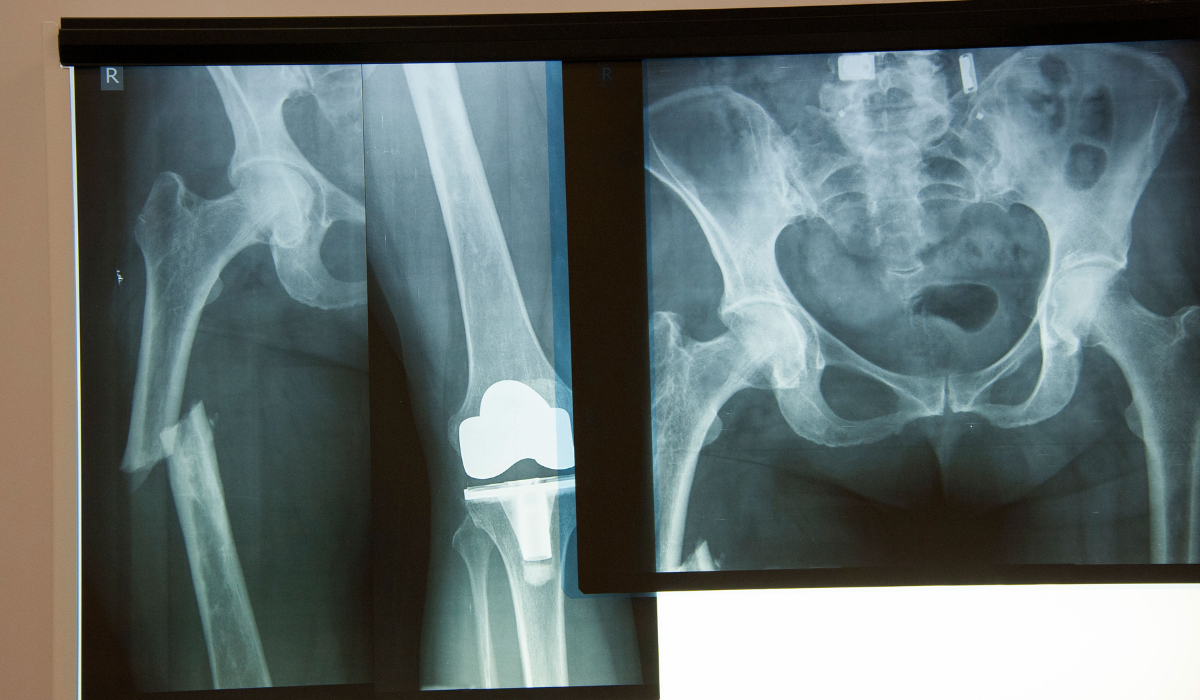

We offer comprehensive care for hip fractures—from diagnosis to surgery and post-operative rehabilitation. The process begins with clinical assessment, X-rays, and sometimes CT scans to evaluate the fracture type. Based on the findings, our orthopedic team develops a tailored surgical plan. Internal fixation is preferred for non-displaced or stable fractures, using metal screws, rods, or plates to hold the bone together.

For displaced or severe fractures—especially in older adults—partial or total hip replacement is recommended. In hemiarthroplasty, the femoral head is replaced with a prosthesis, while in total hip replacement, both the femoral head and hip socket are replaced. These procedures are performed under spinal or general anesthesia with precision and care.

Internal fixation stabilizes the bone using screws/rods, while hip replacement involves replacing part or all of the hip joint.